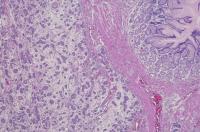

NEW YORK NY (Dec. 15, 2016)—Gastric tumors are started by specialized cells in the stomach that signal nerves to make more acetylcholine, according to a study in mice. The multinational team of researchers who conducted the study also identified a substance called nerve growth factor that stimulates nerve development and, when blocked, inhibits stomach cancer development.

Through a series of experiments in mouse models, the researchers determined that a neurotrophin (substance that triggers nerve growth) called nerve growth factor is highly expressed in gastric cancer cells. They also discovered that tuft cells—specialized cells found in the lining of the digestive tract that, like nerves, communicate with other cells—provide another source of acetylcholine for cancer cell growth, particularly during the formation of tumors.

“We learned that tuft cells are increased during the earliest stage of gastric tumor development, making acetylcholine and stimulating the production of nerve growth factor within the lining of the stomach,” said Dr. Wang. “As nerves grow in around the tumor, tuft cells decrease.”

In additional experiments, the scientists showed that overexpression of nerve growth factor in the mouse stomach drove tumorigenesis. Furthermore, administration of a nerve growth factor receptor inhibitor prevented stomach cancer in the mice.